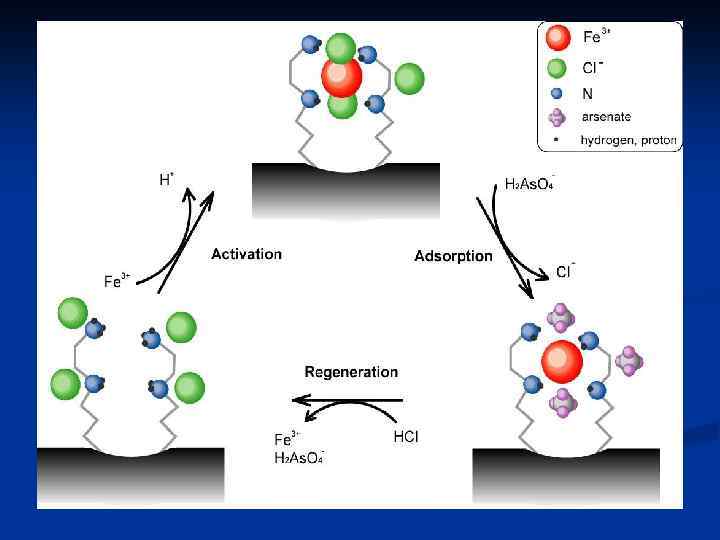

n Гемосорбцияны қандағы әр түрлі зиянды заттардан тазарту үшін қолданады. Ағзада әдетте бұл бауырдың жұмысы. «Гемо» -қан, «сорбция» -ағзаны уландырушы зиянды заттардан тазарту, яғни қанды, қан сары суын, лимфаны токсиндерден, улы заттардан тазарту үшін сорбентпен толтырылған арнаулы түтік арқылы сүзгіден өткізілуі.